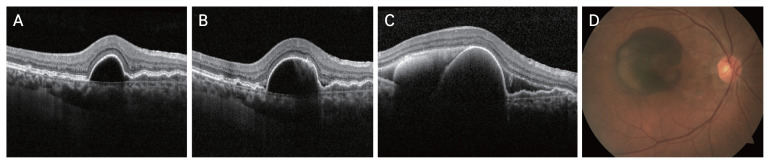

{"title":"Predictive Factors for Submacular Hemorrhage in Age-related Macular Degeneration: A Retrospective Study.","authors":"Hanwool Moon, Hyun Goo Kang, Junwon Lee, Christopher Seungkyu Lee, Min Kim, Suk Ho Byeon, Sung Soo Kim","doi":"10.3341/kjo.2024.0032","DOIUrl":null,"url":null,"abstract":"<p><strong>Purpose: </strong>Little is known about the major risk factors for submacular hemorrhage (SMH). This study aimed to evaluate the factors associated with SMH in patients with neovascular age-related macular degeneration (nAMD) and polypoidal choroidal vasculopathy receiving three consecutive loading doses of intravitreal aflibercept or ranibizumab injections.</p><p><strong>Methods: </strong>This retrospective cross-sectional study included 48 patients diagnosed with nAMD and polypoidal choroidal vasculopathy who completed three loading doses under a treat-and-extend regimen. Patients were divided into the SMH group and the non-SMH group (age- and sex-matched without SMH), with 24 patients in each group. Intravitreal injections, agents, and optical coherence tomography (OCT) features were compared.</p><p><strong>Results: </strong>In the SMH group, SMH occurred approximately 3.29 years after post-nAMD diagnosis. The non-SMH group received more intravitreal injections of aflibercept and brolucizumab during the follow-up period after the initial loading phase. The SMH group exhibited a higher prevalence of serous/hemorrhagic pigment epithelial detachments (PEDs) at the last visit before SMH occurrence compared to the non-SMH group. Patients with a PED increase in the past two visits showed a higher tendency in the SMH group. No other OCT features significantly correlated with SMH development.</p><p><strong>Conclusions: </strong>The presence of serous/hemorrhagic PEDs may indicate a higher risk of SMH, and eyes with these features should be closely monitored to prevent sudden and devastating visual loss caused by SMH.</p>","PeriodicalId":101356,"journal":{"name":"Korean journal of ophthalmology : KJO","volume":" ","pages":"471-479"},"PeriodicalIF":0.0000,"publicationDate":"2024-12-01","publicationTypes":"Journal Article","fieldsOfStudy":null,"isOpenAccess":false,"openAccessPdf":"https://www.ncbi.nlm.nih.gov/pmc/articles/PMC11647097/pdf/","citationCount":"0","resultStr":null,"platform":"Semanticscholar","paperid":null,"PeriodicalName":"Korean journal of ophthalmology : KJO","FirstCategoryId":"1085","ListUrlMain":"https://doi.org/10.3341/kjo.2024.0032","RegionNum":0,"RegionCategory":null,"ArticlePicture":[],"TitleCN":null,"AbstractTextCN":null,"PMCID":null,"EPubDate":"2024/10/22 0:00:00","PubModel":"Epub","JCR":"","JCRName":"","Score":null,"Total":0}

Purpose: Little is known about the major risk factors for submacular hemorrhage (SMH). This study aimed to evaluate the factors associated with SMH in patients with neovascular age-related macular degeneration (nAMD) and polypoidal choroidal vasculopathy receiving three consecutive loading doses of intravitreal aflibercept or ranibizumab injections.

Methods: This retrospective cross-sectional study included 48 patients diagnosed with nAMD and polypoidal choroidal vasculopathy who completed three loading doses under a treat-and-extend regimen. Patients were divided into the SMH group and the non-SMH group (age- and sex-matched without SMH), with 24 patients in each group. Intravitreal injections, agents, and optical coherence tomography (OCT) features were compared.

Results: In the SMH group, SMH occurred approximately 3.29 years after post-nAMD diagnosis. The non-SMH group received more intravitreal injections of aflibercept and brolucizumab during the follow-up period after the initial loading phase. The SMH group exhibited a higher prevalence of serous/hemorrhagic pigment epithelial detachments (PEDs) at the last visit before SMH occurrence compared to the non-SMH group. Patients with a PED increase in the past two visits showed a higher tendency in the SMH group. No other OCT features significantly correlated with SMH development.

Conclusions: The presence of serous/hemorrhagic PEDs may indicate a higher risk of SMH, and eyes with these features should be closely monitored to prevent sudden and devastating visual loss caused by SMH.